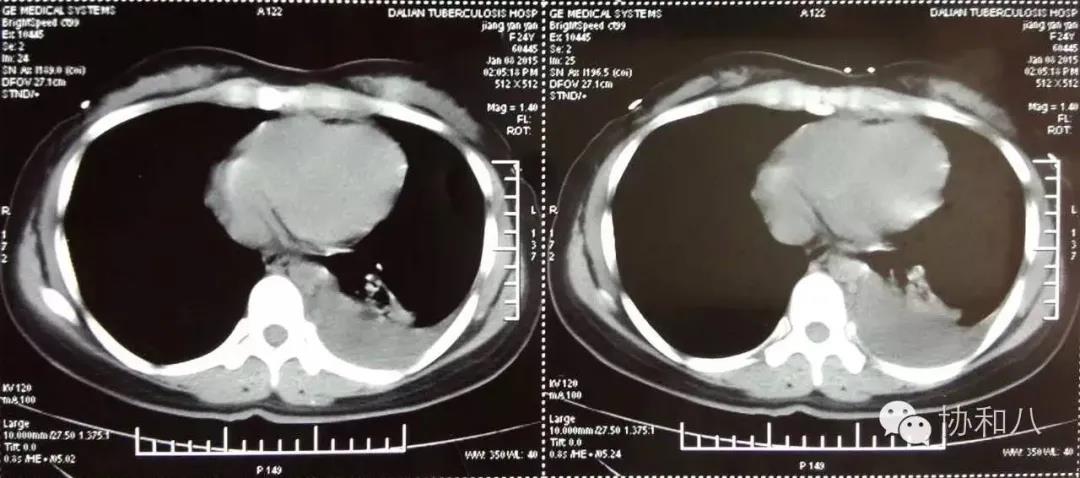

病例介绍患者女性,23 岁。主诉:胸痛、发热 9 月,肢端增粗 7 月,关节肿痛 2 月 。 1病史2014 年 12 月,出现左侧胸痛、胸闷;伴午后低...